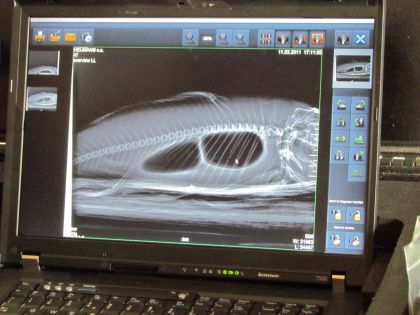

A conferma di questo, l'ultima parte del corso di oggi verteva proprio sull'utilizzo della massima strumentazione messa oggi a disposizione dei veterinari specializzati su questo tipo di pesci. Per quesro motivo ci è stata data la possibilità di provare strumenti quali endoscopi, ecografi e di affettuare radiografie..

...dalla eccezionale risoluzione.

Interessantissimi sono i molti casi riscontrati in cui la vescica natatoria si riempie di acqua. Non è ancora nota la causa ma accade che l'acqua penetra all'interno dell'esofago ed allaga la vescica natatoria. Poiché il pesce non ha più la possibilità di riempire la vescica per stabilizzarsi in acqua e di contrastare la forza di gravità, i sintomi tipici di questa patologia sono lo stazionamento sul fondo con le pinne aperte a guisa di appoggio e la necessità di rimanere in movimento per galleggiare. La diagnosi può essere più approfonditamente confermata con raggi x ed ultrasuoni ed il trattamento prevede l'aspirazione di tutta l'acqua contenuta nella vescica ed il successivo riempimento con una corretta quantità di aria. Ovviamente solo un medico veterinatio esperto, dotato della necesaria struetazione, può effettuare un'operazione di quasto tipo.